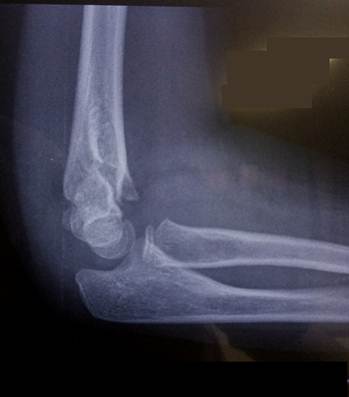

Область локтя в разном возрасте

Василий Оскарович Маркс говорил, что неподготовленный человек на

снимке локтевого сустава здорового ребенка найдёт восемь переломов. Очень даже

может быть – рентгенологическая картина локтя ребенка в возрасте от года до

четырнадцати лет насыщена ядрами окостенения и зонами роста, которые легко

принять за костный отломок или осколок, особенно если в анамнезе есть травма.

Иногда

трудности с интерпретацией рентгенологической картины локтевого сустава

возникают даже у многоопытных специалистов. И что тогда делать? – Надо сделать

рентгенограммы противоположного, здорового сустава и сравнить. Но в большинстве

случаев внимательное изучение анамнеза, клинической картины и рентгенограммы

позволяет принять правильное решение и без этого.

Мы

думаем, что все, кто имел дело с детской травмой, согласятся с нами, что для

детей являются типичными переломы нижнего конца плечевой кости: чрезмыщелковые

переломы, переломы головчатого возвышения и блока, переломы надмыщелков.

Причиной тому является обилие хрящевой ткани в составе нижнего конца плечевой кости

и нежность структур, которые она формирует. По своей сути это даже не переломы,

а остеоэпифизеолизы. Механизм травмы простой – падение с упором на руку. Да,

может произойти перелом дистального отдела лучевой кости подобно тому, как это

бывает у взрослых. Но там хрящ достаточно толстый и мощный, не так-то просто

его сломать. А вот локоть… Дети в возрасте от 3 до 12 лет именно его и ломают.